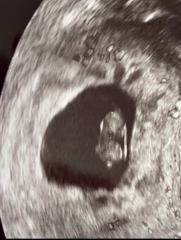

Been looking at my only ultrasound image of ‘nugget’ and realise I don’t actually know what I’m looking at.

Can anyone with knowledge of reading ultrasound images please help? Can you tell from this image which end is baby’s head? Not sure why it matters but for some reason it does.

@DevonEma Not an ultrasound expert but from the pictures I think on the left one your baby's head is the too part of the baby and the second picture shows the baby on his or her side with their head to the left. That's what I see but I could be wrong,